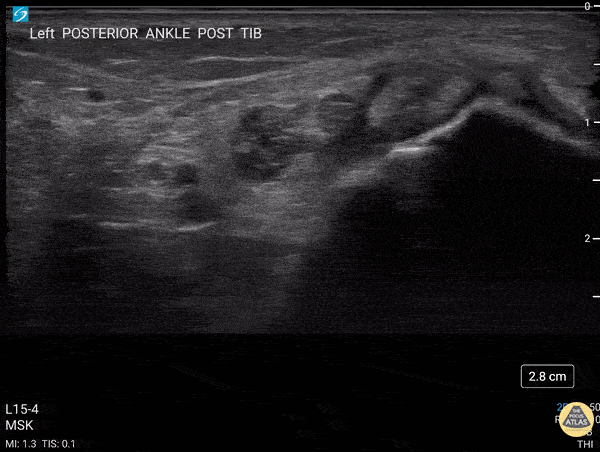

40 y/o F presented with 9 month history insidious onset L medial ankle pain and was found to have tibialis posterior tendon partial tear. Video shows transverse view scanning proximal to distal at the posteromedial ankle (left is posterior). There is thickening of the posterior tibialis tendon with an anechoic tendon sheath effusion. At the level of the medial malleolus there are two moderate interstitial tears extending distally. Flexor digitorum and hallicus longus appear unaffected. Eben Alexander, DO Devesh Patel, MD Eastern Virginia Medical School